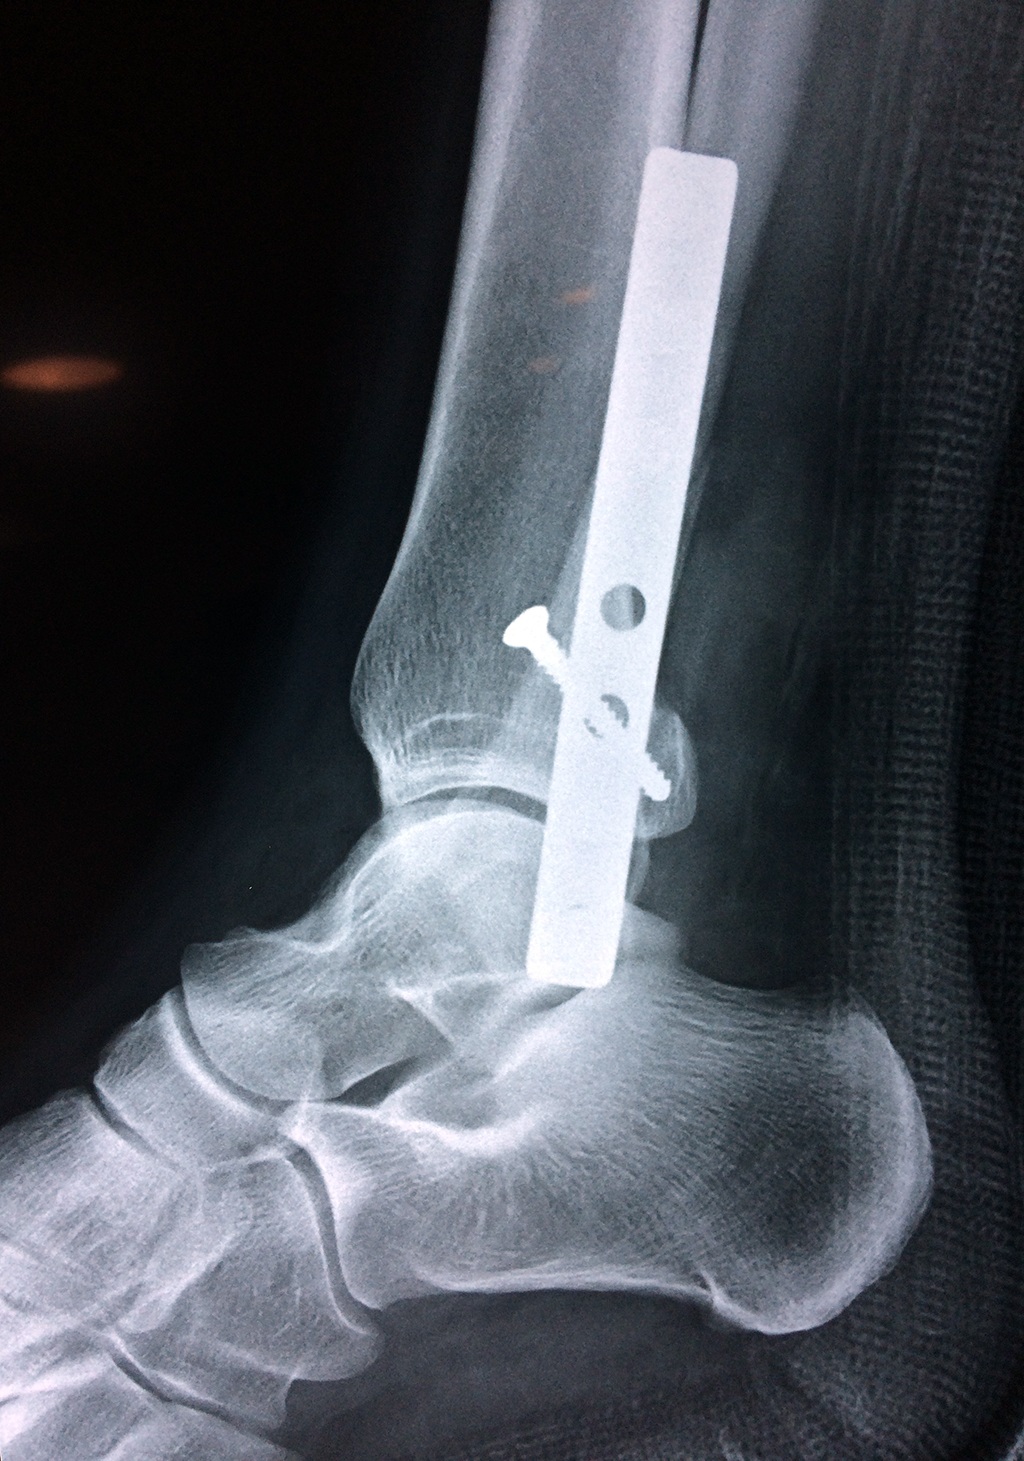

Cuando se necesita cirugía, es probable que esta implique el uso de clavijas de metal, tornillos o placas para sostener los huesos en su lugar mientras la fractura se consolida. Los elementos de soporte pueden ser temporales o permanentes.